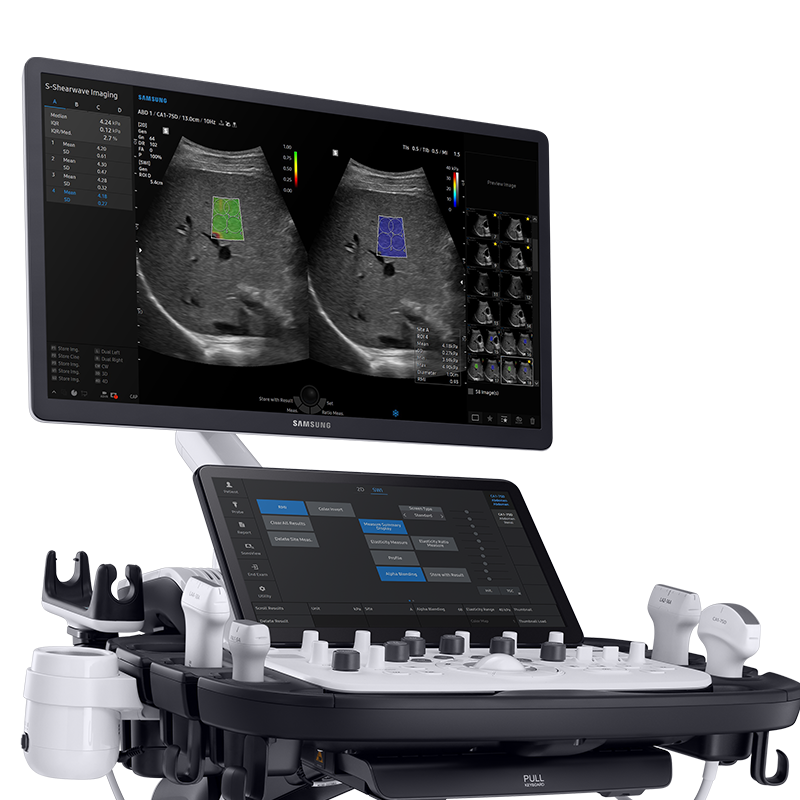

S-Shearwave

Evacuation non invasive de la dureté des tissus.